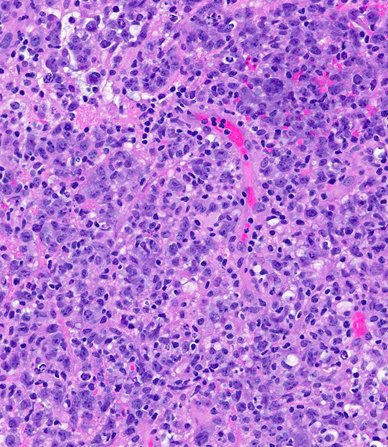

A male patient in his 40s presented to outside hospital after developing left facial droop, slurred speech and urinary incontinence while traveling. The medical history was remarkable for Tdap vaccination administered three days prior to the commencement of his symptoms. MRI of the brain and spinal cord showed multifocal enhancing confluent white matter lesions. He was diagnosed with acute disseminated encephalomyelitis (ADEM). He was subsequently started on high-dose steroids (solumedrol 1 gram) daily x five days followed by a steroid taper. After returning home he presented to Cedars-Sinai ED one month later with similar symptoms of worsening slurred speech and altered gait. He was again started on steroids with improvement of his symptoms and was discharged home but was admitted again two weeks later with worsening symptoms. MRI imaging showed multifocal supratentorial and infratentorial parenchymal T2/FLAIR signal abnormality involving the cerebral hemispheres, deep gray/white matter, corpus callosum (splenium) and brainstem white matter tracts, raising suspicion for neoplastic process [left image, upper panel]. He was placed on IVIG (2 grams/kg) over five days and was continued on prednisone 60 milligrams daily. Serum autoimmune encephalopathy panel, NMO and MOG cell-based assays were all negative. Ultimately, he underwent a brain biopsy which showed involvement by diffuse large B-cell lymphoma [right image]. It was BCL6 rearranged by FISH while NGS identified mutations in CDKN2A, PIM1, CD79B, CTCF, ATM and SOCS1.

Central nervous system diffuse large B-cell lymphoma accounts for <1% of all non-Hodgkin lymphomas and ~3% of all brain tumors. Primary diffuse large B-cell lymphoma (DLBCL) of the CNS is defined as DLBCL arising within the brain, spinal cord, leptomeninges or eye. Primary diffuse large B-cell lymphoma of the CNS excludes lymphomas of the dura, intravascular large B-cell lymphomas, lymphomas with evidence of systemic disease or secondary lymphomas, and all immunodeficiency-associated lymphomas. In immunocompetent individuals the etiology of this disease is unknown. Patients usually present with cognitive dysfunction, psychomotor slowing and focal neurologic symptoms. For detecting CNS DLBCL, magnetic resonance imaging (MRI) is the most sensitive technique. The gold standard for establishing diagnosis is a stereotactic biopsy with microscopic review showing highly cellular diffusely growing large cells. On immunohistochemistry the tumors are PAX5+, CD19+, CD20+, CD22+, CD79a+, and kappa or lambda light chain restricted. In addition, most cases express BCL6 as well as MUM1. Prognosis is worse in patients with CNS DLBCL than patients with systemic DLBCL. Other negative prognostic factors include older age (>65 years) and del(6)(q22). Currently the treatment of choice for these patients is high-dose methotrexate-based polychemotherapy. With treatment the median progression-free survival is 12 months with the overall survival rate being approximately three years. Lastly, some sporadic systemic relapses have been observed with the most frequent relapses involving the testis and breast.